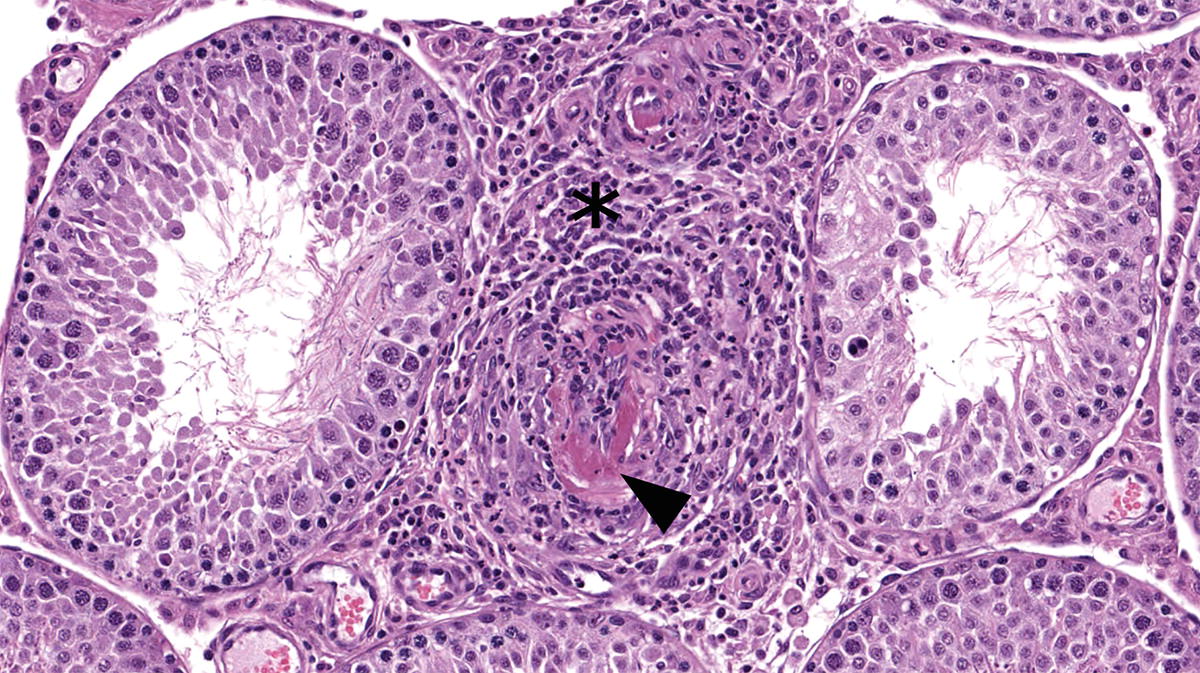

In cats a small prostrate gland surrounds the point of entrance of the two ductus deferens and the adjacent urethra. At the caudal end of the pelvic canal a pair of cowpers glands enter the urethra canal. What male reproductive gland is missing in the cat but present in the human. They are glands that secrete a significant amount of fluid that becomes the semen.

The prostate gland surrounds the beginning portion of the urethra and the termination of the ductus deferens. If only one testicle is affected the cat will still be fertile. The epididymis connects the testicle to the ductus deferens which carries ejaculated sperm to the urethra. In male cats the genital tract provides a pathway for semen which contains the sperm cells.